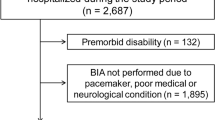

This is a retrospective analysis of prospectively collected data from 255 screened consecutive patients with nontraumatic SAH admitted to the neurocritical care unit of a tertiary referral center between April 2010 and November 2016. The study was approved by the ethics committee of the Medical University of Innsbruck (AN3898 285/4.8). Informed consent was obtained from all patients according to federal regulations. Inclusion criteria were the diagnosis of nontraumatic SAH, patient age above 18 years, and the availability of noncontrast enhanced head CT scans performed on admission and at least one performed 5–9 days or 12–16 days after admission. Patients were excluded if they were admitted to the neurocritical care unit 2 or more days after the hemorrhage, if they were transferred to another unit within 7 days of admission, and if the available CT scans were of insufficient quality for the measurement of temporal muscle volume.

Of 255 screened consecutive patients with nontraumatic SAH, 98 didn’t meet inclusion criteria, 33 were excluded due to insufficient quality of cerebral CT scans, 12 were excluded due to early transfer to another ward, and 2 were excluded due to late admission, leaving 110 patients for final analysis.